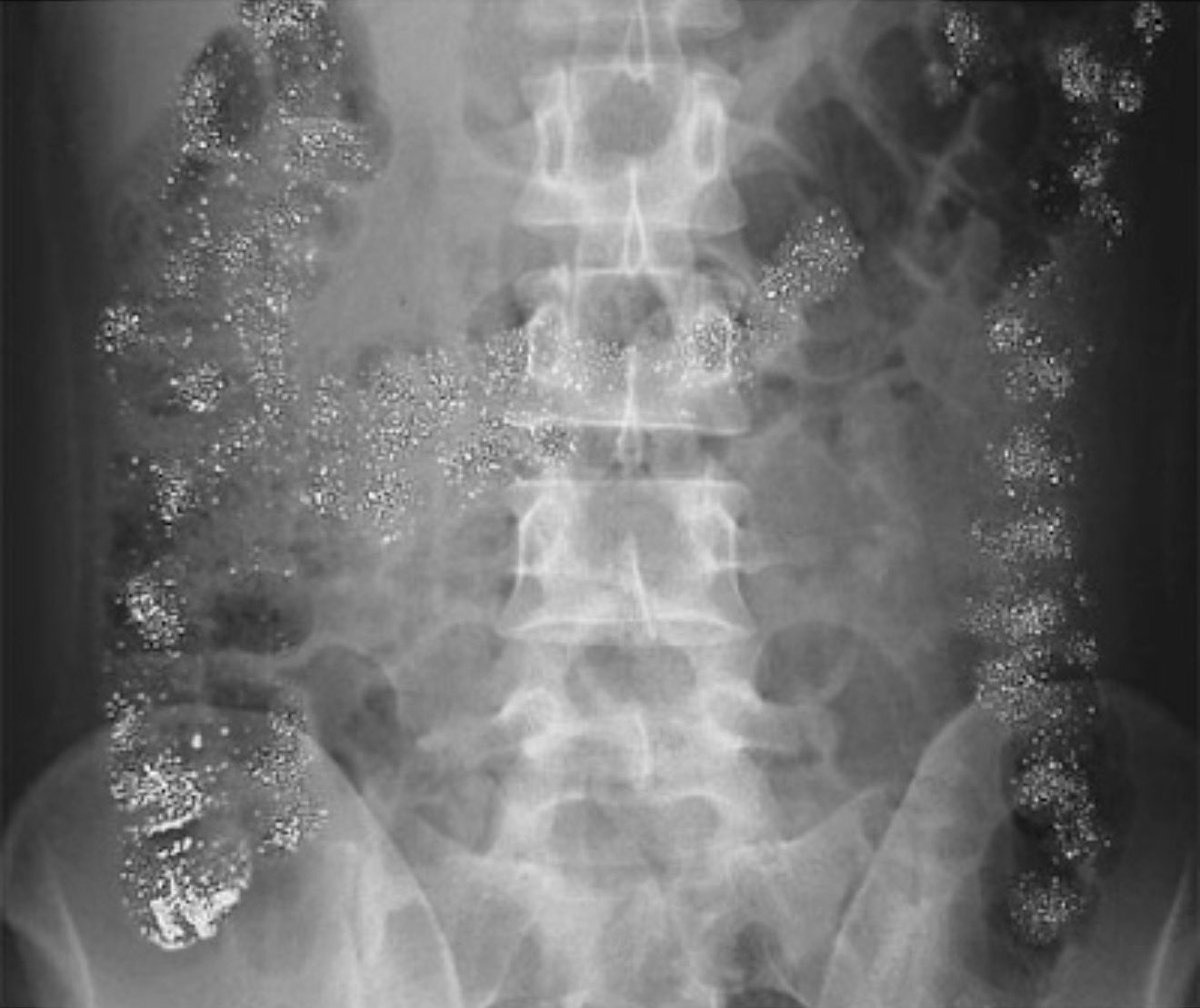

How do you explain this abdominal X-ray?

drkeithsiau's tweet image. How do you explain this abdominal X-ray?